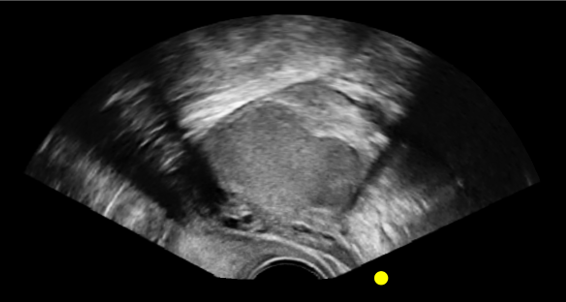

This comprehensive Endometriosis eLearn and simulation module is designed to support clinicians and Allied Health Professionals in developing the skills needed to identify endometriosis during transvaginal ultrasound. Using authentic ultrasound images, the module provides structured, step-by-step training that reflects real-world clinical scenarios and common disease presentations in the pelvis.

Our guided-learning replicates the experience of learning directly from a specialist. Available on each case*, the system provides highlighted ultrasound imagery with clear annotations, allowing learners to gain a clear understanding of what they are looking at, and what to look for in clinical practice – bridging the gap between theory and hands-on practice.

Dynamic highlighting and guided pathways encourage learners to progress at their own pace while reinforcing correct technique. This approach ensures that complex concepts – such as recognising anatomical variations or subtle signs of pathology – are made accessible, consistent, and clinically relevant. With our guided-learning, every scan becomes a repeatable opportunity to build skills under the guidance of an expert.